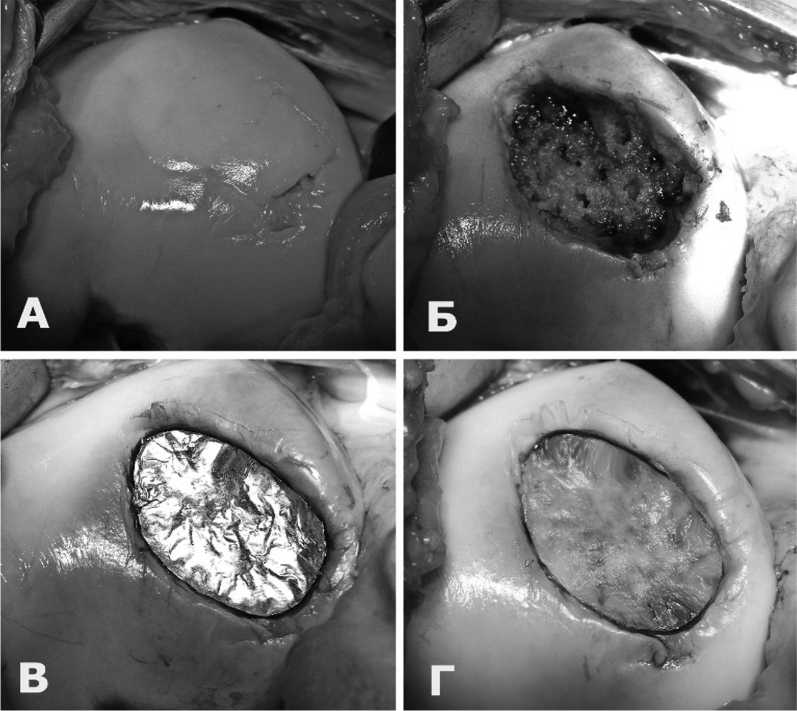

В тех случаях, когда имелся обширный дефект хряща – 3-7см², артроскопия завершалась и дальнейшие этапы операции выполнялись открытым способом (рис. 2А). Еще раз хотим обратить внимание, что имплантация мембраны допускается только на здоровую и кровоснабжаемую субхондральную кость.

Производилась санация (выравнивание) хряща по краям дефекта и удаление поверхностного слоя измененной субхондральной кости до кровоточащих слоев (рис. 2Б). Спицей диаметром 2,4мм выполняли рассверливание здоровой субхондральной кости на глубину 1-1,5 см (рис. 2В) Успехом этой манипуляции следует считать обильное кровотечение из сформированных отверстий.

Коллагеновая мембрана моделировалась по форме и размеру дефекта хряща. На субхондральную кость по краям дефекта наносили фибриновый клей. Мембрана укладывалась пористой поверхностью на субхондральную кость, расправлялась и плотно прижималась к кости (рис. 2Г). После полимеризации фибринового клея, что занимало 3-5 минут, проверялась прочность и стабильность фиксации коллагеновой мембраны.

Рис. 2. Этапы операции AMIC. А – дефект до санации. Б – дефект после санации. В – дефект после туннелизации субхондральной кости. Г – имплантирована коллагеновая мембрана

Fig. 2. Stages of AMIC operation. A – defect before sanitation. B – defect after reorganization. Б – defect after tunnelization of the subchondral bone Г – a collagen membrane is implanted